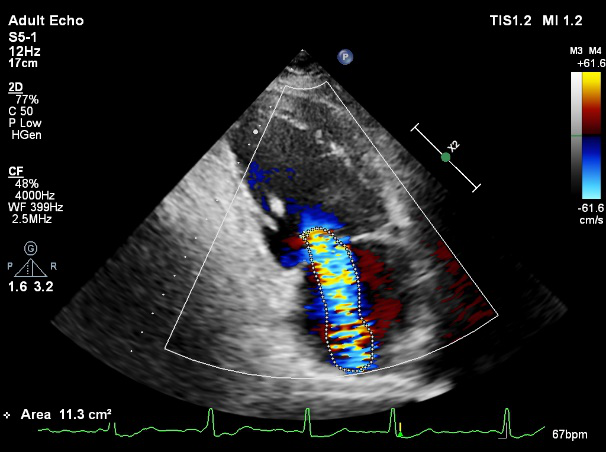

术前超声诊断

LVOT-color:MR(重度),返流面积11.3cm2

肺静脉血流频谱呈收缩期反向

3D-color MV view:血流主要来源于2、3区

Qlab软件勾画估测瓣口面积约:6.16cm2

TEE LVOT切面返流量评估

TEE 4-Ch view返流量评估